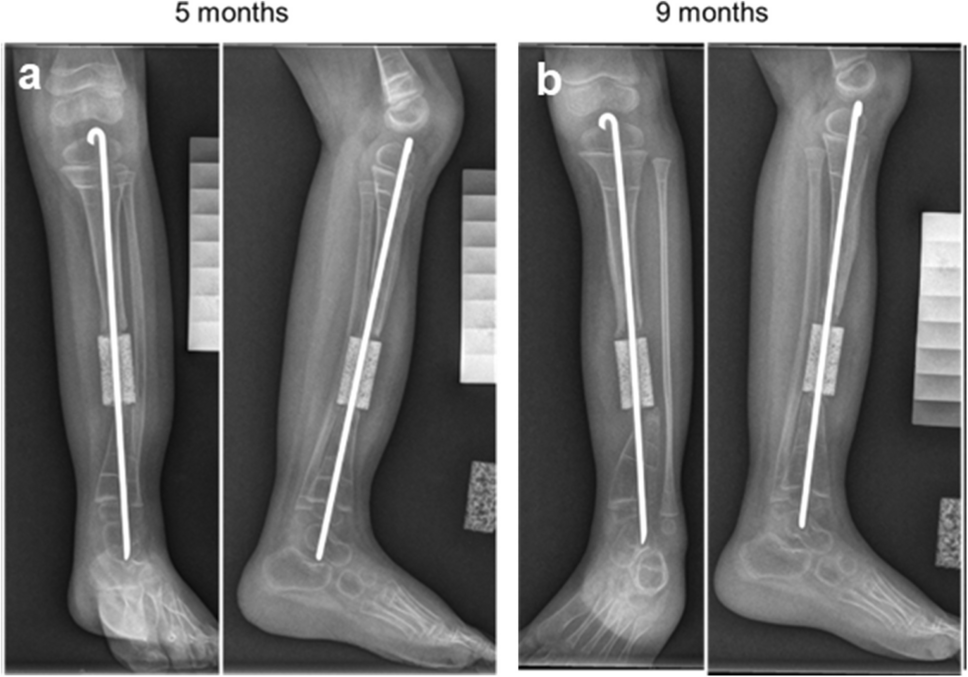

Safety Evaluation of Autologous Human Bone Marrow-derived MSCs on Hydroxyapatite-based Scaffold for Congenital Pseudarthrosis of the Tibia: A Pilot Clinical Trial

Congenital pseudarthrosis of the tibia (CPT) is a rare genetic disease characterized by impaired periosteal bone tissue re...